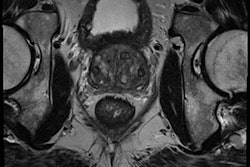

A novel MR imaging technique known as restriction spectrum imaging (RSI) can accurately differentiate aggressive prostate cancer from low-grade or benign tumors, according to a study published in the June 1 issue of Clinical Cancer Research.

Researchers from the University of California, San Diego (UCSD) and the University of California, Los Angeles (UCLA) found that RSI can also help guide biopsies and subsequent treatment (Clin Cancer Res, June 1, 2016, Vol. 22:11, pp. 2668-2674).

RSI-MRI corrects for magnetic field distortions found in other imaging techniques and focuses on water diffusion within tumor cells that exhibit a high nuclear volume fraction. This enables RSI to more accurately plot a tumor's location and allows for differentiation between tumor grades.